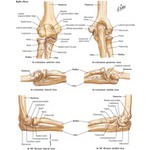

Bones of Elbow

Bones of Elbow

Labeled - Cleland Ortho Clinical Exam 1E